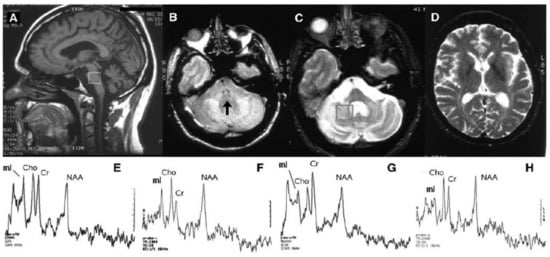

- Guerrini, L.; Lolli, F.; Ginestroni, A.; Belli, G.; Della Nave, R.; Tessa, C.; Foresti, S.; Cosottin, M.; Piacentini, S.; Salvi, F.; et al. Brainstem neurodegeneration correlates with clinical dysfunction in SCA1 but not in SCA2. A volumetric, diffusion and quantitative proton spectroscopy MR study. Brain 2004, 127, 1785–1795. [Google Scholar]

- Boesch, S.M.; Schocke, M.; Bürk, K.; Hollosi, P.; Fornai, F.; Aichner, F.T.; Poewe, W.; Felber, S. Proton magnetic resonance spectroscopic imaging reveals differences in spinocerebellar ataxia types 2 and 6. J. Magn. Reson. Imaging 2001, 13, 553–559. [Google Scholar] [CrossRef] [PubMed][Green Version]

- Viau, M.; Marchand, L.; Bard, C.; Boulanger, Y. 1H magnetic resonance spectroscopy of autosomal ataxias. Brain Res. 2005, 1049, 191–202. [Google Scholar] [CrossRef] [PubMed]

- Oz, G.; Iltis, I.; Hutter, D.; Thomas, W.; Bushara, K.O.; Gomez, C.M. Distinct neurochemical profiles of spinocerebellar ataxias 1, 2, 6, and cerebellar multiple system atrophy. Cerebellum 2011, 10, 208–217. [Google Scholar] [CrossRef]

- Lirng, J.F.; Wang, P.S.; Chen, H.C.; Soong, B.W.; Guo, W.Y.; Wu, H.M.; Chang, C.Y. Differences between spinocerebellar ataxias and multiple system atrophy-cerebellar type on proton magnetic resonance spectroscopy. PLoS ONE 2012, 7, e47925. [Google Scholar] [CrossRef]

- Adanyeguh, I.M.; Henry, P.G.; Nguyen, T.M.; Rinaldi, D.; Jauffret, C.; Valabregue, R.; Emir, U.E.; Deelchand, D.K.; Brice, A.; Eberly, L.E.; et al. In vivo neurometabolic profiling in patients with spinocerebellar ataxia types 1, 2, 3, and 7. Mov. Disord. 2015, 30, 662–670. [Google Scholar] [CrossRef]